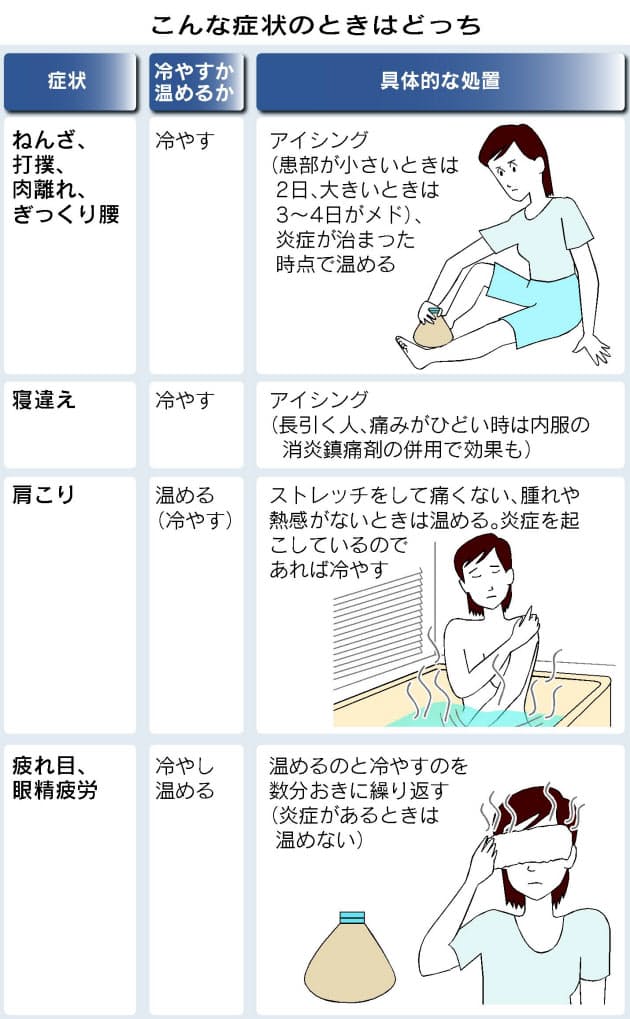

ねんざや肩こり 冷やす 温める 対処法の基本 Nikkei Style

捻挫(ねんざ)したらどうする? 捻挫(ねんざ)は、とくに足首や指に起こりやすく、関節をひねって痛めてしまうことで起こります。 靭帯の損傷などが考えれらる場合は、整形外科での治療が必要です。 目立った腫れやひどい痛みといった症状がなければセルフケアで様子をみてもよいでしょう。 捻挫(ねんざ)直後の応急処置や、その後の手当についても · 特に応急処置の際、捻挫の患部に温湿布を貼ることは禁物です。 軽度の捻挫でも、しばらくは飲酒、湯船に浸かる入浴、運動などは避けましょう。 また、立ち仕事も数日は控え、医師の指示に従いながら再開するようにしましょう。2601 · 足首の外側が痛む場合は、 湿布を半分に折って中心部分に切れ込み をいれましょう。

· 足首の捻挫は、湿布を貼ってほっておけば治るものではなく、治療の難しさは、骨折以上に難しいです。 ほかの病院へ行くべきではないかなと思います。 そのときに、足首の捻挫に詳しい先生を捜すべきだと思います。 · 足首の捻挫に湿布は必要ですか? 無事に内出血していれば 患部は腫れていますので 浸出液も必要ですが 腫れを引かせてからの足首の固定が 1番大事ですから湿布を使って腫れを取ります。 腫れが引いて来たならば 冷やすのは止めて温湿布に切り替えます。 · 効果的な湿布の貼り方 捻挫や打撲などで熱をともなうときは冷湿布を使います。 冷湿布は冷蔵庫で保存しておくと、より効果的です。 湿布の形は2タイプあり、急性の痛みにはパップ剤、慢性的な痛みにはテープ剤が良いとされています。